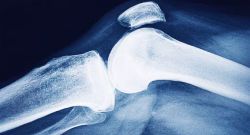

Osteoporosis weakens bone and exposes people to so-called “fragility” fractures (a fall from standing height, a trivial movement). Long asymptomatic, it often declares itself with a first fracture – vertebra, wrist, hip – which is likely to be followed by others if nothing is done. Each October, the International Osteoporosis Foundation ...